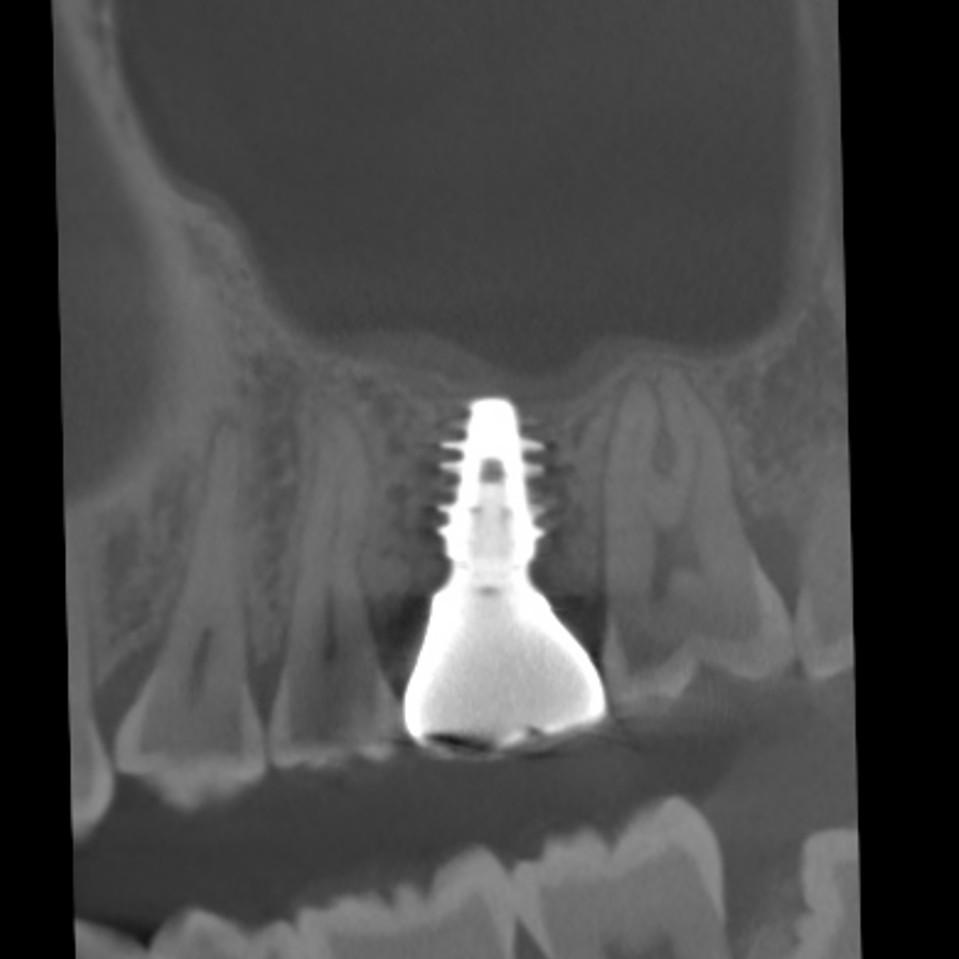

このように健康な歯が真っ二つに割れることはめったにないのですが、こうなると神経に触る様な強い痛みが出ますし、CTスキャンをとると上顎洞炎にもなっていました。

上の奥歯は上顎洞までの距離が短くインプラントが難しいことも多いのですが、即時埋入用に開発されたインプラントを使えば抜歯と同時にインプラント埋め込みまで行うことができると判断しました。

CTスキャンで確認してみても上顎洞炎もきれいに治っていることが分かります。